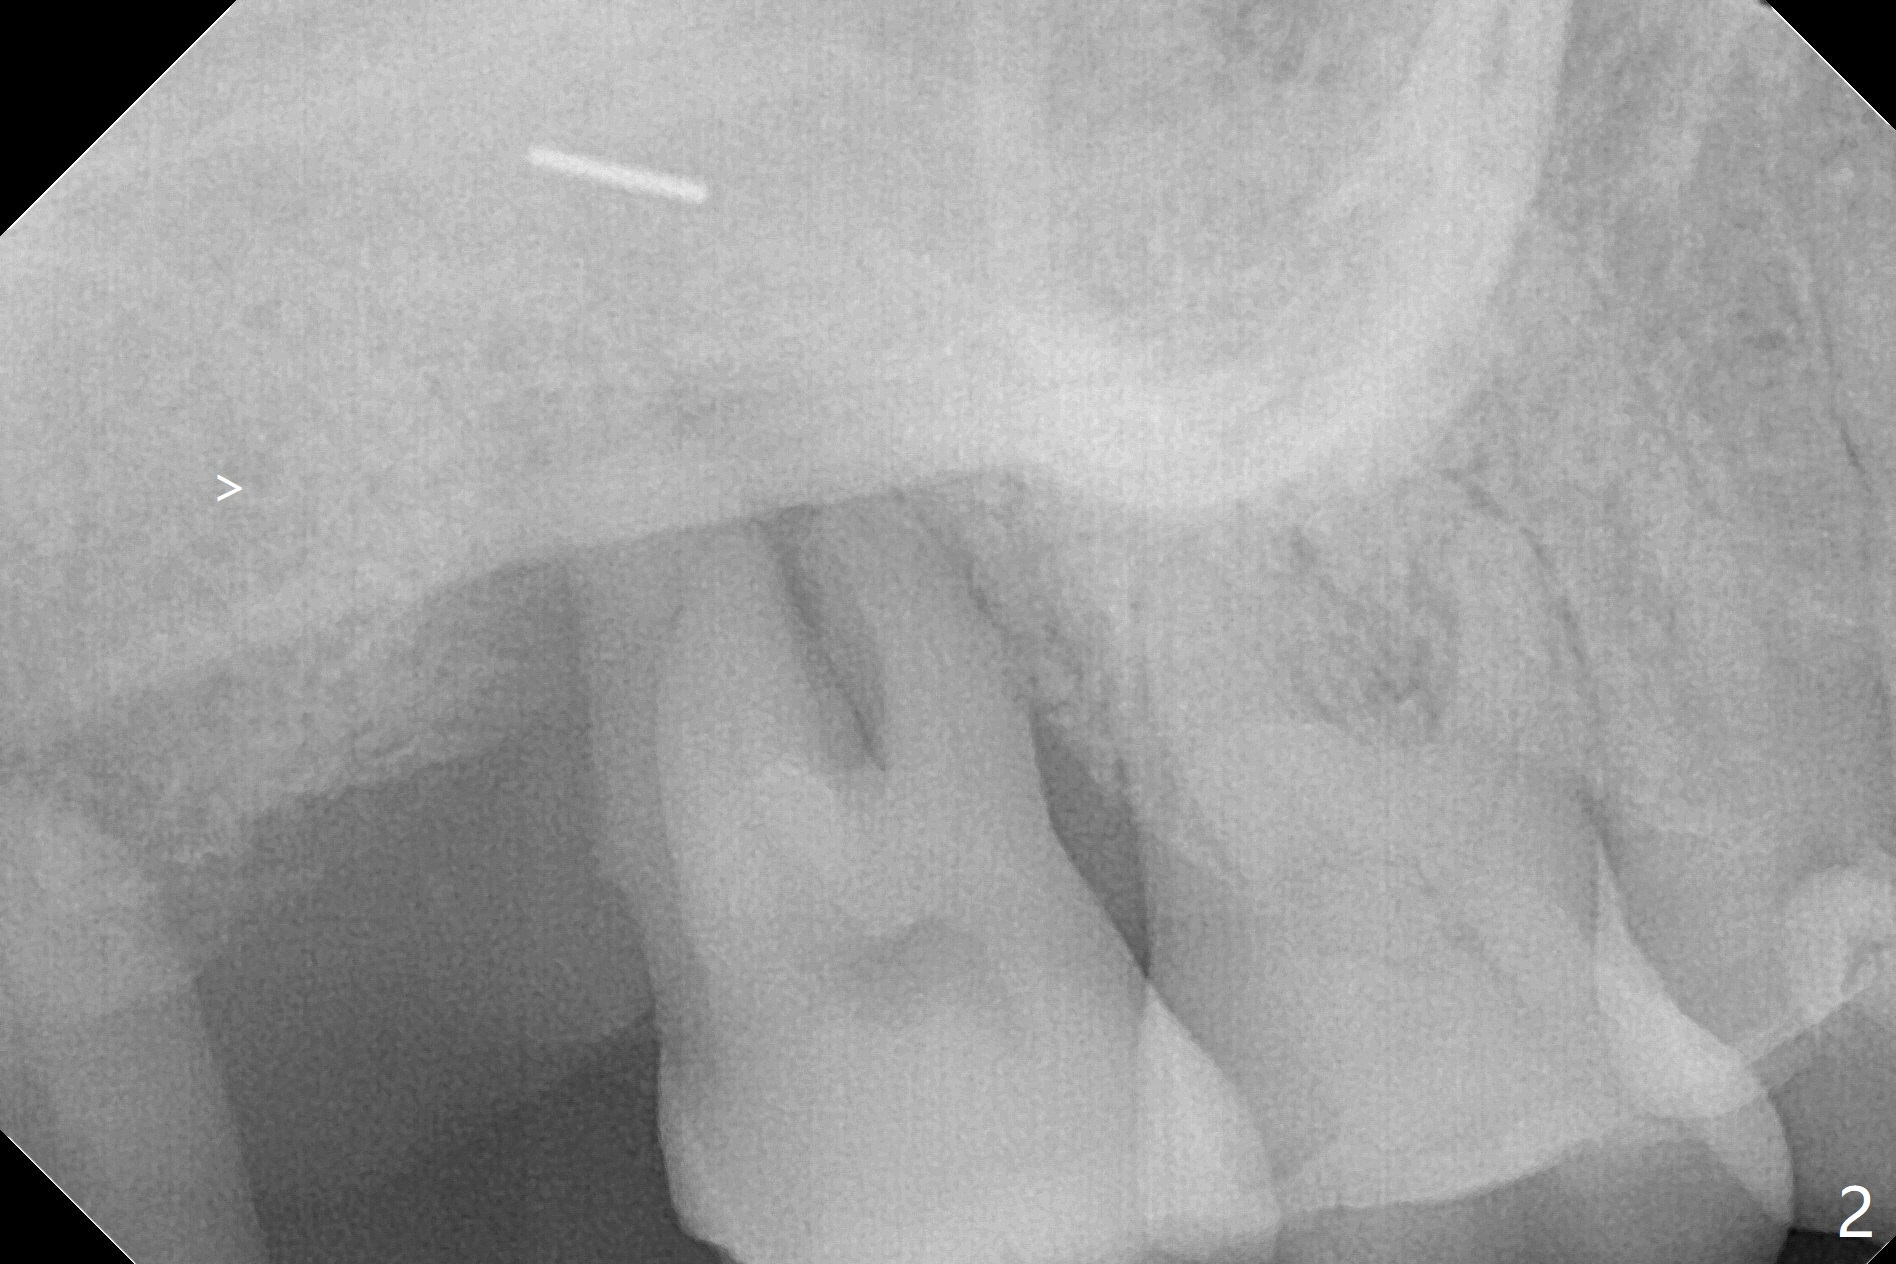

59岁女两年前就诊,主诉右上7,8之间食物坎塞,没有注意7骨质吸收(图一),以为是8过度延申所致拔除,而且远中颊侧,腭侧根断裂(间接说明咬合力大),前者拔除,而后者滞留。如果不拔除,现在支撑导板多好。两年后病人认为断根长出来,其实腭侧根尖仍在骨中(图二(半年前拍摄):箭头),而7骨质吸收更严重,松动2度,怀疑根裂(咬合力大)。同时病人可能有骨质疏松,拔除即刻种植,基台一定要短,一旦牙槽窝愈合,考虑取出临时牙冠,减少微动。取模前,进行渐进性负荷。术前服用Z Pack,准备上颌窦提升,PRFx2。CT显示上颌窦提升不需要,植体可以植入腭侧窝(图三)。 CT冠状切面(图四),矢状切面(图五)显示必须使用长袖的基台(粉红色)固定粘性骨粉(红色),这样植体(绿色)稍微可以种得浅些。箭头:cotton roll(颊侧牙龈沟)。为了让病人在制作导板时舒服些,利用邻牙做冠外固定7松动牙(III)。7颊侧软组织缺失(图六:*)。